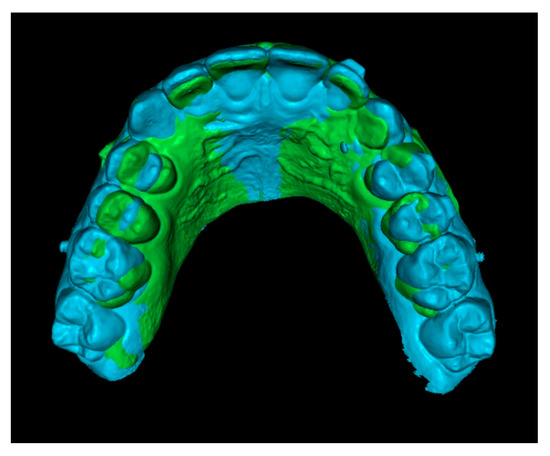

Third step: Overlay of Initial STL with IC and Final STL.

The initial STL combined with the IC was superimposed onto the final STL by marking stable reference points on the palatal rugae (Figure 6). This process resulted in a final STL model that includes the initial position of the IC (Figure 7).

Figure 6.

Superimposition of initial and final STL models using palatal rugae.

Figure 7.

Final STL including the initial 3D position of the IC.